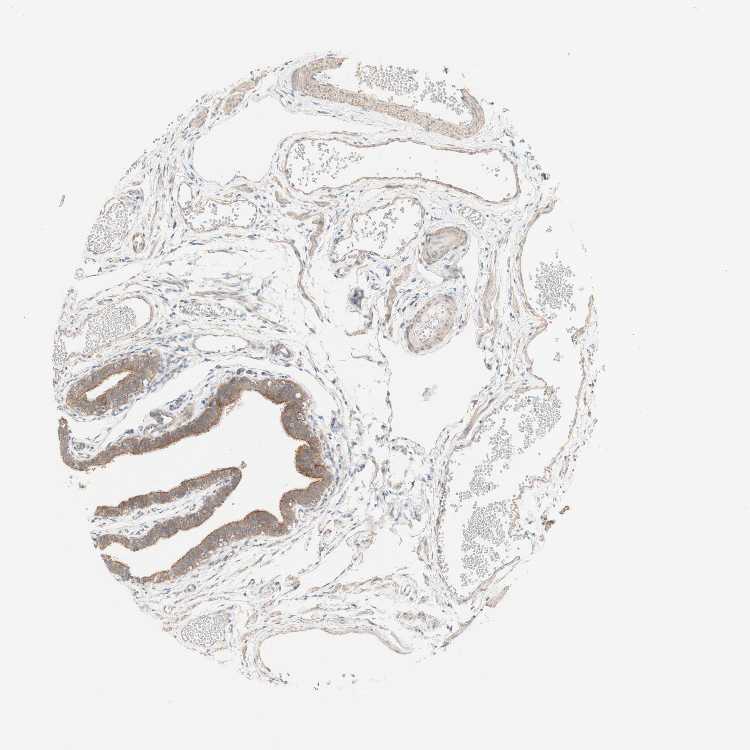

TISSUE PRIMARY DATA FALLOPIAN TUBE Show tissue menu

FALLOPIAN TUBE - Antibody stainingi

Antibody staining in the annotated cell types in the current human tissue is reported as not detected, low, medium, or high, based on conventional immunohistochemistry profiling in selected tissues. This score is based on the combination of the staining intensity and fraction of stained cells.

Each image is clickable and will lead to virtual microscopy that enables deeper exploration of all samples and also displays staining intensity scores, fraction scores and subcellular localization as well as patient and tissue information for each sample.

Antibody HPA001813Antibody CAB009228

Glandular cells MediumMedium